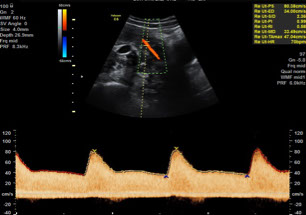

Ultraschall

- Nierenultraschall zum Ausschluss Harnstau

- Schwangerschaft, inklusive Farbdoppler und 3D Babyfernsehen